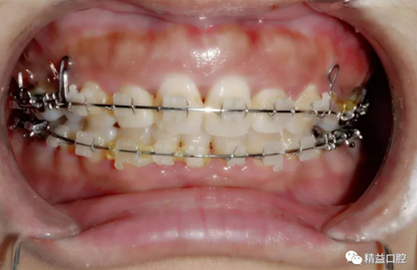

為了保證矯正效果和整體牙齒健康,李醫(yī)生在矯正過程中不斷根據(jù)每次牙齒移動的情況,對所施加的矯正力以及每次復(fù)診的時間進行精細(xì)的調(diào)整,在放慢矯正速度的同時,以更加輕柔的力量來拉動牙齒移動。事實證明一切OK,上牙的內(nèi)收效果非常的好。

內(nèi)收過程中,李醫(yī)生在上頜左右各植入一顆支抗釘,以達到更好的內(nèi)收效果。

短短兩年時間,俊嚴(yán)重前突的牙齒在經(jīng)過拔牙,打支抗釘,打各種曲,戴各種皮筋的“不斷折騰”下,完美蛻變。